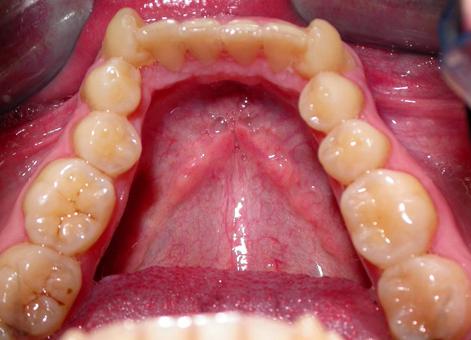

Пациент обратился с диагнозом индивидуальная макродентия.

Диагностика дополнительно выявила:- тенденцию к формированию мезиальной окклюзии,

- сужение и укорочение зубных рядов,

- ретрузию верхних центральных резцов,

- мезиальное смещение боковых отделов нижнего зубного ряда,

- ретрузию нижних резцов,

- множественные аномалии положения зубов.